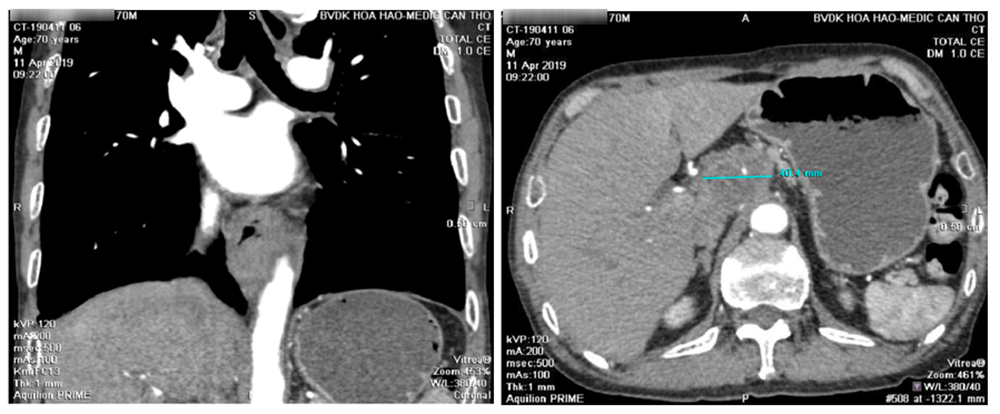

Msct toàn thân có tiêm thuốc cản quang

Dầy thành thực quản 15mm kéo dài 1/3 cuối thực quản, bắt thuốc cản quang mạnh, chùm hạch lớn vùng đầu tụy 5cm